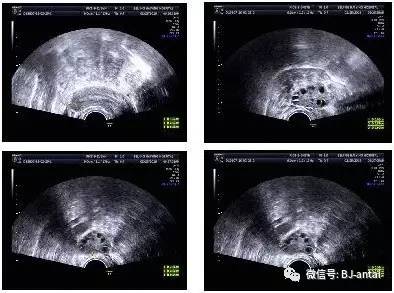

【读片】典型多囊卵巢

图片尺寸640x512